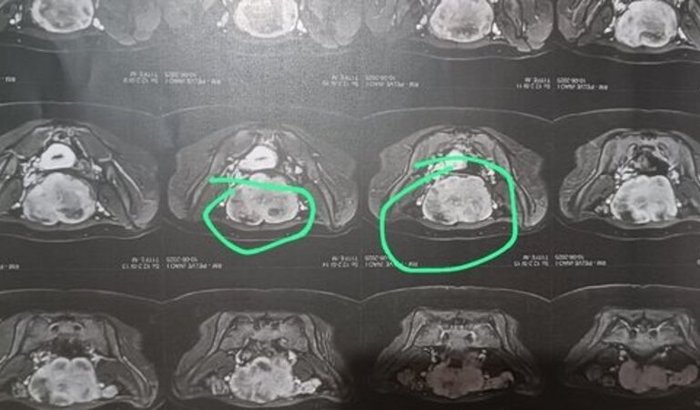

Olá, meu nome é Jhonatas e minha esposa precisa de retirada de nódulo no ovário que está ja em 11 entímetros, e que vale 6 mil, falta so 2 mil, se conseguir qualquer valor vai estar salvando a vida dela, Deus abençoe. ver tudo

Olá, meu nome é Jhonatas e minha esposa precisa de retirada de nódulo no ovário que está ja em 11 entímetros, e que vale 6 mil, falta so 2 mil, se conseguir qualquer valor vai estar salvando a vida dela, Deus abençoe.